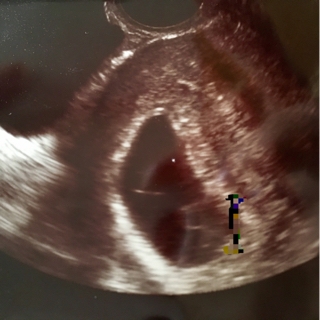

4回目…2月22日

胎嚢25.7mm

胎児4.9mm

かすかな希望と、自分たちの子を信じてあげたいと思って、もう一週間様子を見ることに